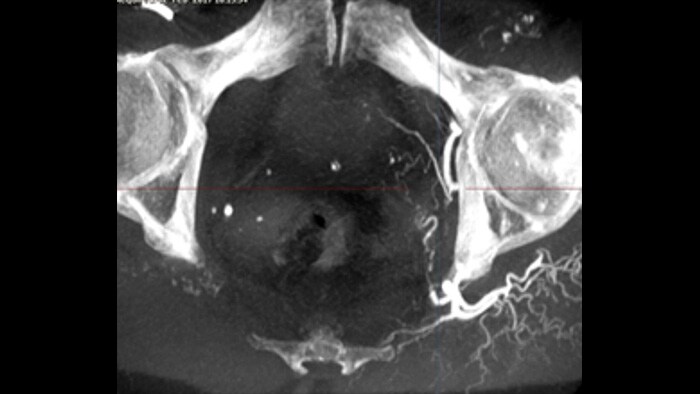

SmartCT Vaso proporciona imágenes 3D de alta resolución que revelan información clave sobre las estructuras vasculares cerebrales para apoyar la mayor evaluación espacial posible del contexto de los vasos.

Esta técnica de adquisición de rayos X genera una vista completa en 3D de alta resolución de la vasculatura cerebral, cardíaca, abdominal o periférica a partir de una única serie de angiografía rotativa, todo ello controlado a través de la pantalla táctil de la mesa. Esto puede hacer que se vean mejor las características anatómicas enrevesadas o complejas que puede no apreciarse en una imagen 2D o una ASD.